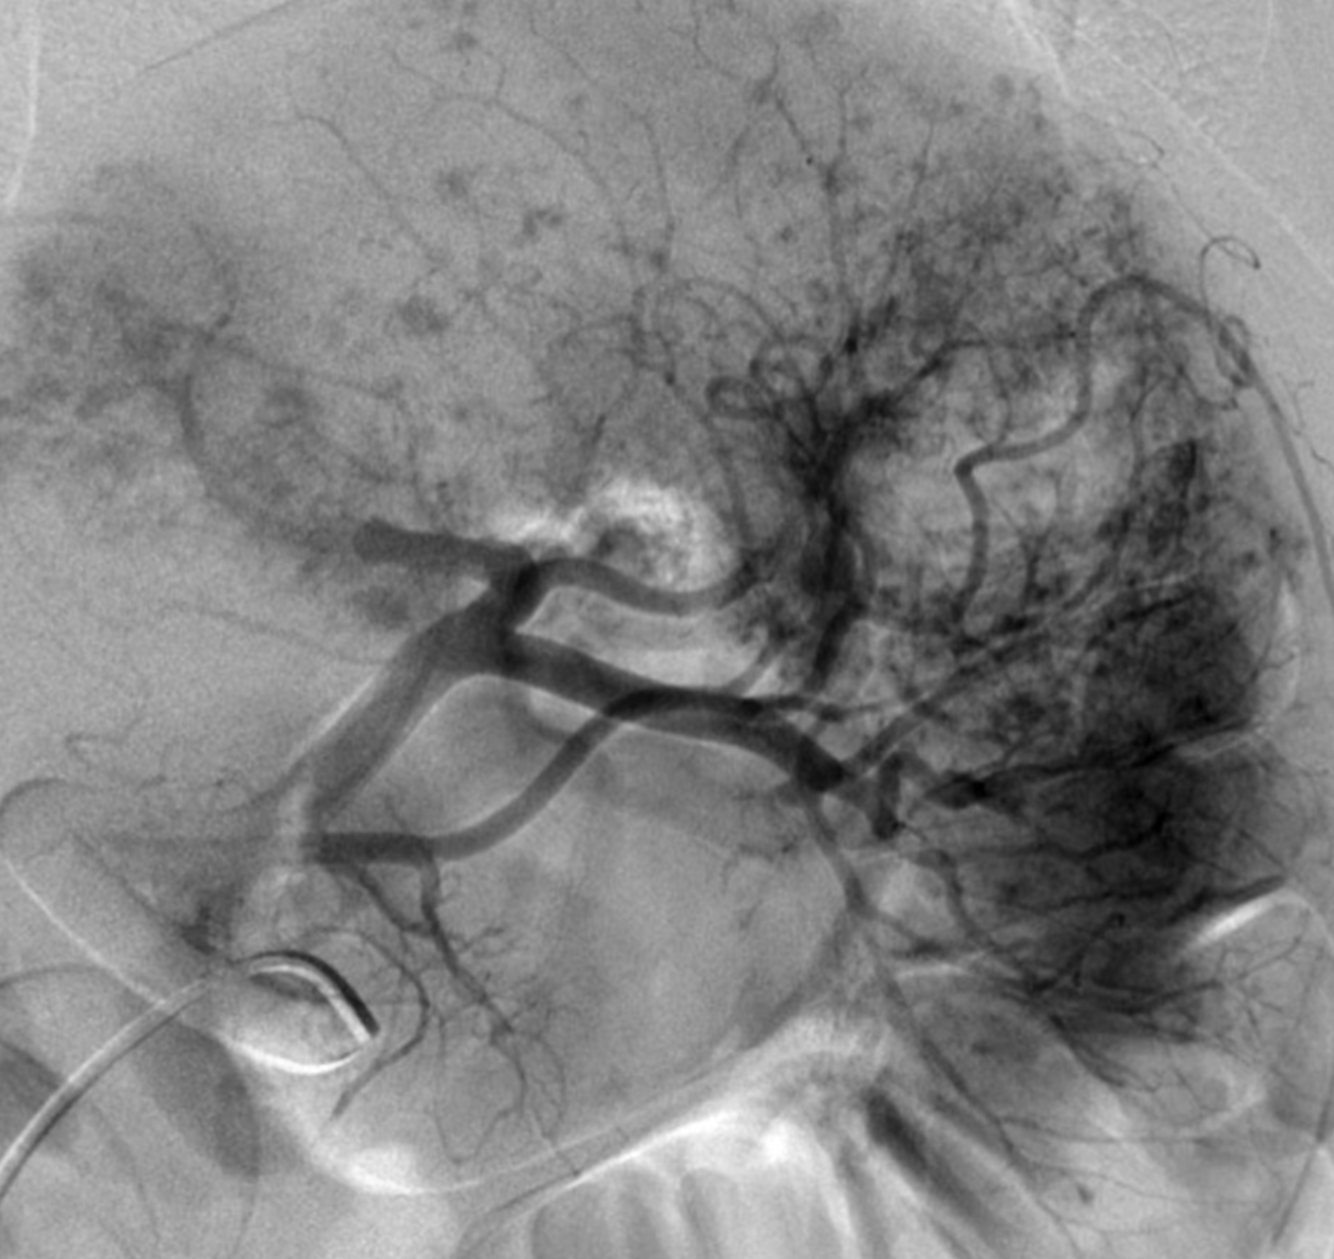

“Gray weather, Grande Jatte” by Georges Seurat, painted 1888.

Case Discussion

Innumerable small punctate contrast extravasations in a traumatised spleen following motor vehicle accident. This angiographic appearance is often termed ‘Seurat spleen’ because of a likeness to the artwork of French impressionist Georges Seurat (1859 - 1891) who used a pointillistic technique to create an image out of tiny dots. Proximal splenic artery embolisation with coil was performed in this patient who went on to make an uneventful recovery from their splenic trauma.